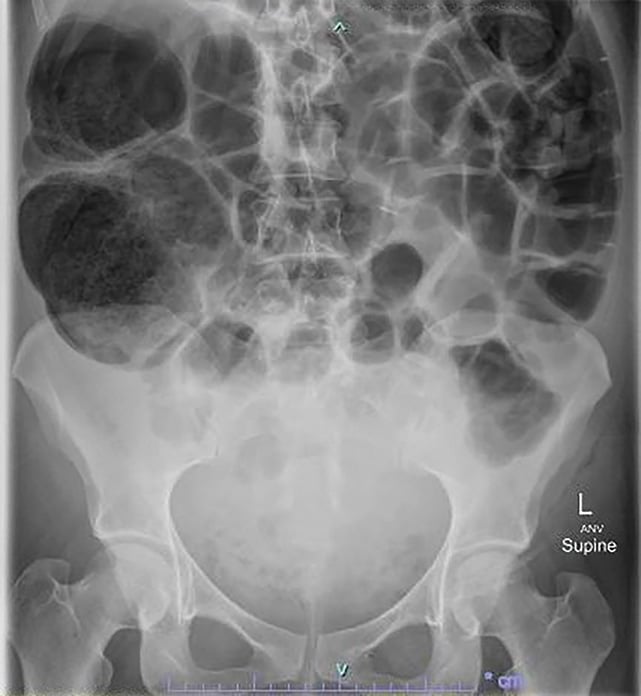

Ogilvie Bowel. In some cases the small bowel.

In some cases the small bowel.

Ogilvie Bowel In some cases the small bowel. In some cases the small bowel.